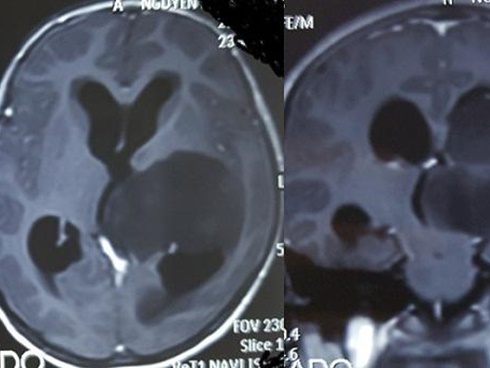

Hình ảnh khối u lớn trong não bệnh nhi (Ảnh: Vietnamnet).